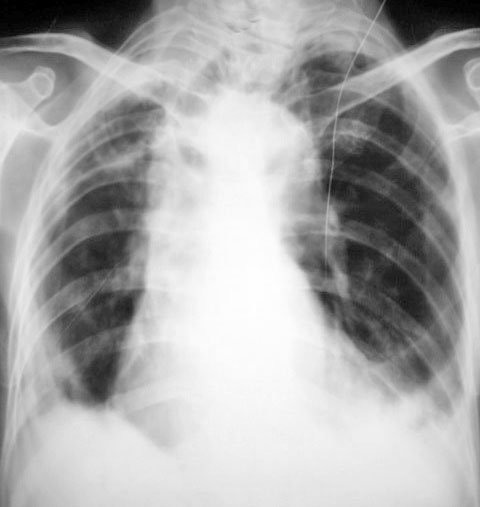

以下是引用小小医在2010-3-16 19:45:00的发言:[br]气管牵拉右移,胸段脊柱右弯畸形,慢性支气管炎,双侧胸膜增厚,左下肺炎,左下胸膜腔少量积液,建议ct

以下是引用随光逐影在2010-3-17 7:43:00的发言:[br]1)右上肺继发性肺结核。2)慢性支气管炎并左下肺感染,肺气肿。3)双侧胸膜增厚,左侧少量胸腔积液。